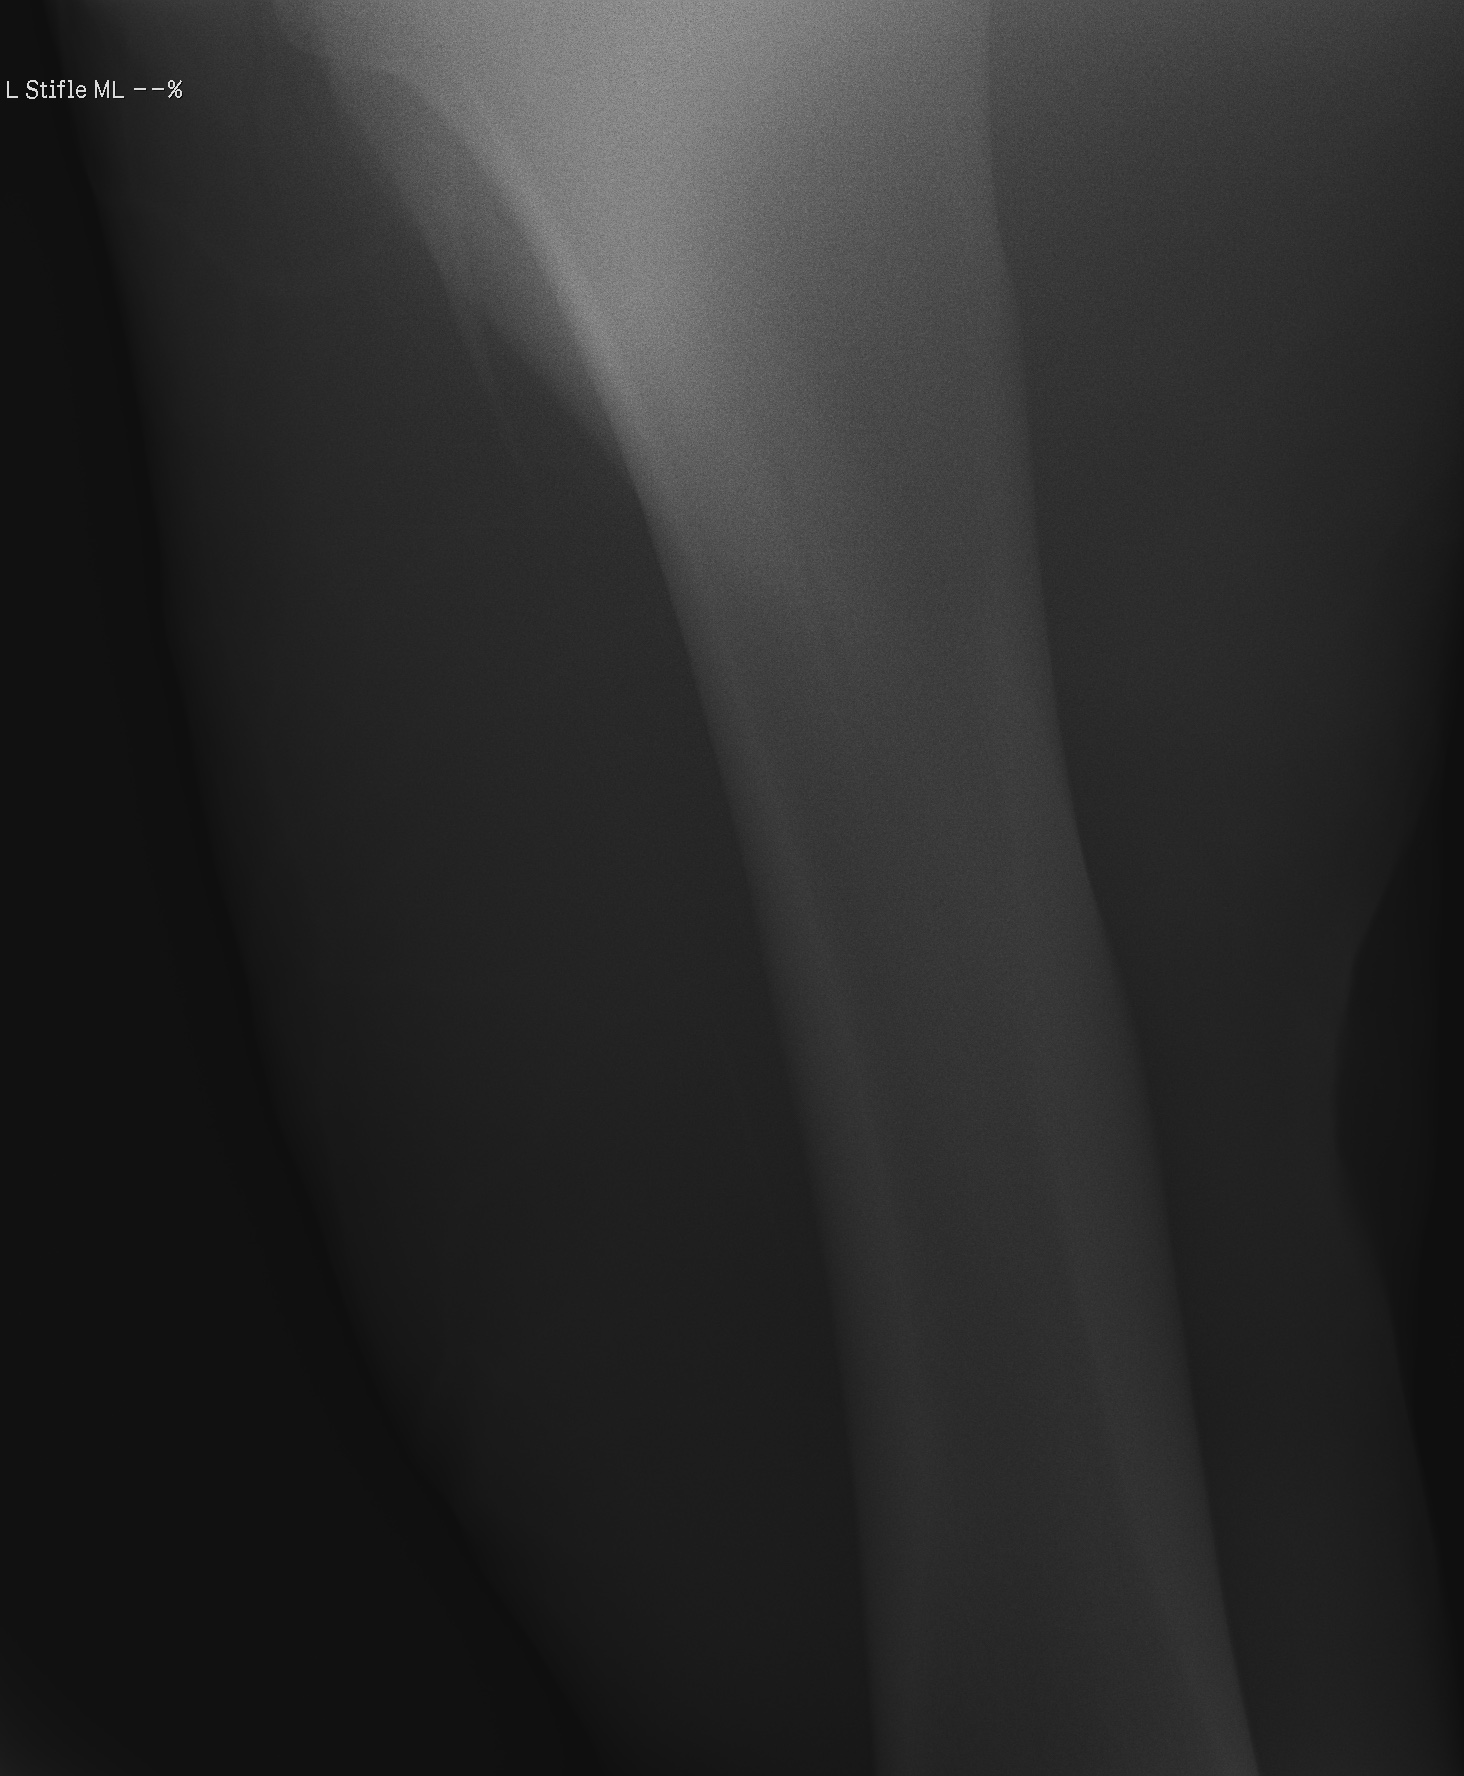

添付のレントゲン画像をご確認ください。現状渡しのノークレームノーリターンでお願いいたします。記載事項に関するキャンセルには応じられません。

※2022年12月17日の競走にて左後脛骨不全骨折を発症しています(全治6~9ヵ月)。